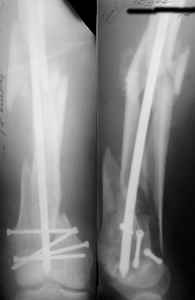

Attached are few examples from our Hospital:

B. Fixation loosening: distal cutting of the nail, non-unions do happen (cases attached).

Locking Plating has more distal screws than any nail, fixed angles and provides much better fixation, especially in osteoporotic bone.